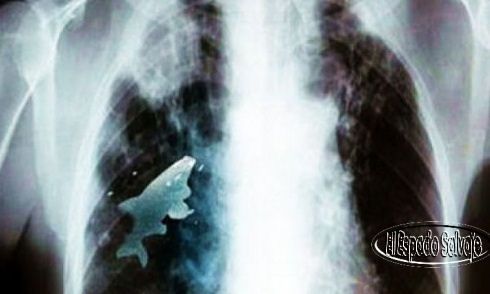

Médicos extraen pez vivo del pulmón de un niño

Esto de jugar a tragarse un pez era un pasatiempo usual de Anil y sus amigos, que pasaban buenos ratos en el río del vecindario, pero esta vez el pez no fue al estómago, sino que lo aspiró y terminó en su pulmón izquierdo a través de la tráquea, según publicó The Nation, un periódico de Pakistán.

Poco después el niño empezó a tener dificultades para respirar y fue trasladado al hospital de su localidad, donde los médicos verificaron que los niveles de oxígeno en su sangre habían descendido peligrosamente.

Anil fue sometido a una intervención quirúrgica de urgencia que duró 45 minutos y que lo salvó. El pez estaba vivo cuando los cirujanos llegaron a él a través de la broncoscopía.

El doctor  Pramod Jhawar, especialista y experto en broncoscopías que “es el primer caso de este tipo que nos hemos encontrado en 20 años”.